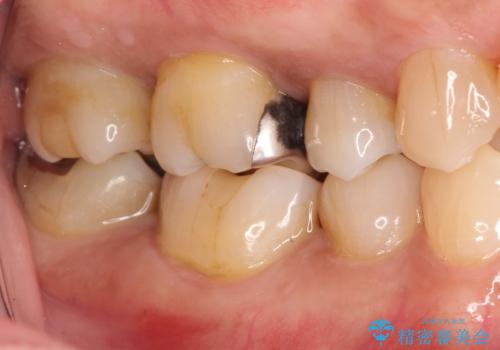

奥歯が痛い。精密根管治療〜オールセラミッククラウン

- 1週間前から冷たいもので強い持続痛を感じることを主訴に来院されました。

歯髄診断と痛みの再現により原因歯を特定し、症候性不可逆性歯髄炎の診断となりました。

根管治療〜オールセラミッククラウン(エクセレント)の治療を行なっております。

- 精密根管治療(イニシャルケース,大臼歯):122,000円、ファイバーコア:22,000円、仮歯:11,000円、オールセラミッククラウン(エクセレント):200,000円費用は治療当時の料金となります